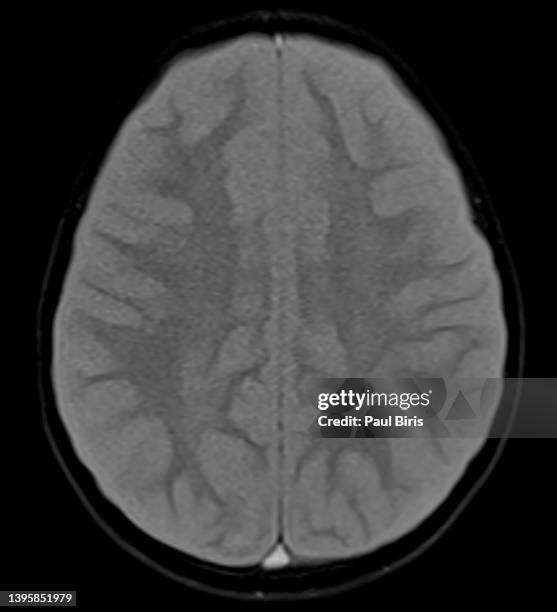

Imaging

Serial neuroimaging (CT scans and magnetic resonance imaging) can be useful in diagnosing or excluding intracranial hemorrhage, large masses, acute hydrocephalus, or brain herniation as well as providing information on the type of edema present and the extent of affected area. CT scan is the imaging modality of choice as it is widely available, quick, and with minimal risks. However, CT scan can be limited in determining the exact cause of cerebral edema in which cases, CT angiography (CTA), MRI, or digital subtraction angiography (DSA) may be necessary. MRI is particularly useful as it can differentiate between cytotoxic and vasogenic edema, guiding future treatment decisions.